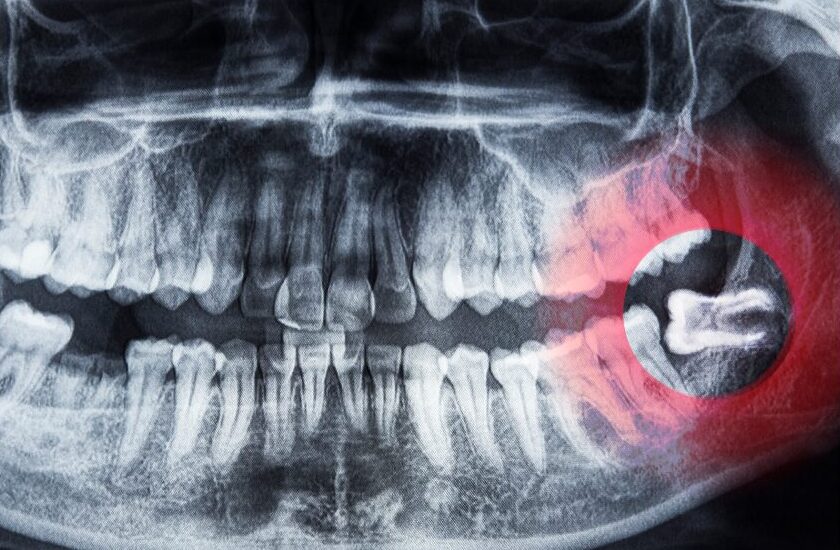

当院での確認ポイント|「抜く/抜かない」はレントゲンで判断します

親知らずは、見えている部分だけでは判断ができません。

- 生え方(まっすぐ/斜め/横向き)